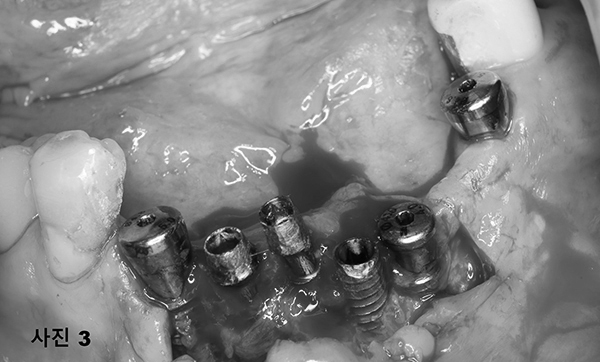

수술 당일 수면마취후 12개의 치아를 다 발치하고 상악에 5개 하악에 4개를 식립하고 (사진3) 왼쪽 마지막 어금니는 단단하여

살리면서 그 상태를 컴퓨터 스캐닝하여 본 병원에서 다음날 (사진4)와 같이 임시 고정성 보철물을 제작하여 심미적 기능과 저작기능을 제공하여 주었다.